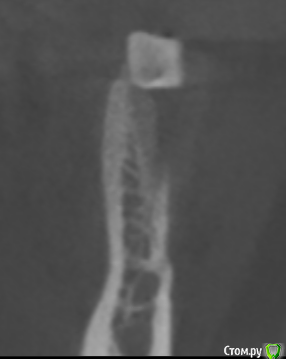

Nazim_NV86 Опубликовано 31 мая, 2018 Поделиться Опубликовано 31 мая, 2018 (изменено) У меня 2 вопроса:1. Что это на дне лунки на первом скрине?2. Что смущает вас на последнем скрине? Я правильно понимаю, туда же надо закрутиться ? Там больше кости и не выросло бы гипотетически. Изменено 31 мая, 2018 пользователем Nazim_NV86 Ссылка на комментарий

kamranchick Опубликовано 31 мая, 2018 Поделиться Опубликовано 31 мая, 2018 У меня 2 вопроса:1. Что это на дне лунки на первом скрине?2. Что смущает вас на последнем скрине? Я правильно понимаю, туда же надо закрутиться ? Там больше кости и не выросло бы гипотетически.1 какули - пломбировочный материал, никак не мог до него дотянутся2, ну да, туда закрутиться, ну я не хотел больше, хотел чтобы хотя бы тот обьем и остался, а в итоге имеем приличную атрофию Ссылка на комментарий

kamranchick Опубликовано 7 июня, 2018 Поделиться Опубликовано 7 июня, 2018 я честно говоря не уловил о чем вы тут ))Я удалил атравматично зубы, сделал пробки и плотно зафиксировал их в лунке, в надежде что останется много чего, но после повторного кт, видим атрофию, да довольно серьезную, в чем оишбка, либо так и должно бьыть Ссылка на комментарий

Bier Опубликовано 7 июня, 2018 Автор Поделиться Опубликовано 7 июня, 2018 а была ли вестибулярная стенка до удаления? Ссылка на комментарий

kamranchick Опубликовано 7 июня, 2018 Поделиться Опубликовано 7 июня, 2018 Кт до Ссылка на комментарий

Bier Опубликовано 7 июня, 2018 Автор Поделиться Опубликовано 7 июня, 2018 да уж, потеря костной ткани значительная...На фейсбуке не выкладывали? Интересно, что у меня получится в моем кейсе. Ссылка на комментарий

Bier Опубликовано 5 июля, 2018 Автор Поделиться Опубликовано 5 июля, 2018 Пообщался с Ромой Новиченко, он сказал, что в таких ситуациях с тонкой-тонкой кортикальной пластинкой нужно "пробку" делать больше, чтобы она заходила немного апикальнее вестибулярного костного края. Ссылка на комментарий

kamranchick Опубликовано 5 июля, 2018 Поделиться Опубликовано 5 июля, 2018 Пообщался с Ромой Новиченко, он сказал, что в таких ситуациях с тонкой-тонкой кортикальной пластинкой нужно "пробку" делать больше, чтобы она заходила немного апикальнее вестибулярного костного края.я даже пол корня оставлял, у меня кость ушла, а десны было вагон, выложу чуть позже кт Ссылка на комментарий